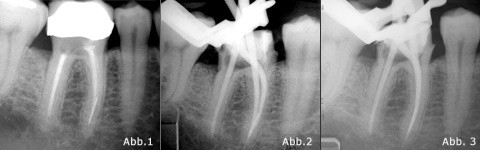

Abb. 1 Ausgangsaufnahme Abb. 2 Masterpointaufnahme exzentrisch. Abb. 3 Masterpointaufnahme orthograd.

Zahn 46 wies in der mesialen Wurzel ein frakturiertes Instrument auf. Der Knochenverlauf wies keine Besonderheiten auf.

Am 11.4.07 stellte sich der Patient erstmalig zur Beratung der Revision vor. Am 16.5.07 erfolgte der erste Teil der Behandlung. Es wurde das Provisorium abgenommen, Kofferdam angelegt und eine Zugangskavität unter dem DM angelegt. Es konnten drei Kanalorificien dargestellt werden. Es erfolgte eine Relocation der Kanaleingänge mittels Gates Glidden Bohrern Nr. 6–4 in absteigender Größe. Im distalen Kanal konnte die Wurzelfüllung mithilfe von ProTaper Revisionsfeilen, C+-Feilen und ultraschallaktivierter 5,25% NaOCl-Spüllösung entfernt werden. Es wurde Patency erzielt, das Shaping erfolgte mit rotierenden ProTaper und ProFiles nach apikalen Gauging bis zur apikalen Aufbereitungsgröße 0.04/60. Im mesio-lingualen Kanal wurde die alte Wurzelfüllung auf dieselbe Weise entfernt. Patency unter elektrometrischer Längenbestimmung konnte erzielt werden und das Shaping erfolgte bis zur Größe 0.06/35. Im mesio-bukkalen Kanal war es nach Entfernen der Guttapercha nicht möglich, das Instrument mit dem DM einzusehen, weshalb keine Entfernung, sondern das Umgehen des Instruments versucht wurde. Mit dem Endo Bender wurden C+-Feilen der Größe 0.06–15 vorgebogen. Mit diesen konnte das Instrument umgangen und auch hier Patency erzielt werden. Das weitere Shaping erfolgte mit vorgebogenen ProTaper Handfeilen bis zur Größe 0.09/30. Es erfolgte eine Masterpointaufnahme. Diese Sitzung wurde mit der ultraschallaktivierten Spülsequenz 5,25% NAOCl, 17% EDTA 5,25% NaOCl und 2% CHX abgeschlossen. Es wurde Ca(OH)2 eingebracht und die Kavität mit Cavit provisorisch verschlossen und das Provisorium wieder eingegliedert.